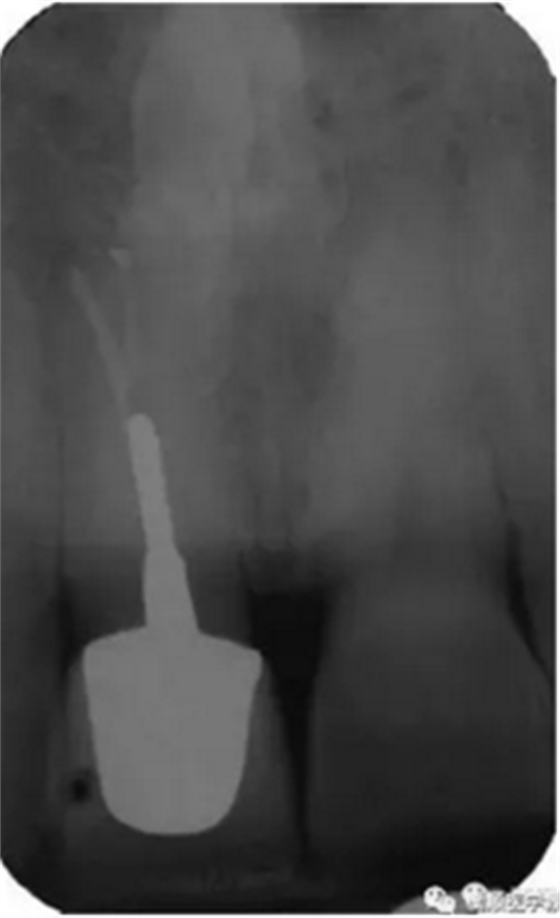

基于臨床檢查和X線(xiàn)片顯示,診斷為右上頜中切牙根尖周炎伴額外牙。治療計(jì)劃是先行患牙的根管治療,制作臨時(shí)義齒,最后制作樁核冠。應(yīng)用橡皮樟和顯微根管技術(shù),利用ProTaper旋轉(zhuǎn)銼配合使用 Hedstrom 銼和桉葉油,將根管內(nèi)充填物取出,觀(guān)察X線(xiàn)片可見(jiàn)根尖三分之一處主根管一分為二,確定另一根管的工作長(zhǎng)度,兩根管同行常規(guī)根管治療,充填后X線(xiàn)片顯示根管充填良好。樁核冠修復(fù)1年后,患牙無(wú)疼痛,影像檢查發(fā)現(xiàn)根尖顯影正常,根尖疾病治愈。

圖3. 樁核冠修復(fù)1年后患牙根尖周顯影